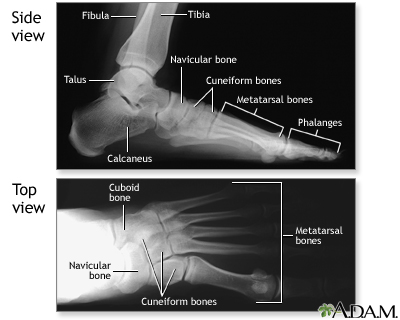

Along with questions of your medical history, your doctor may need to take x-rays of your foot to help aid in making a diagnosis to determine the cause of your foot pain. If the foot is broken it will be put into a cast. Toes that are broken are taped.